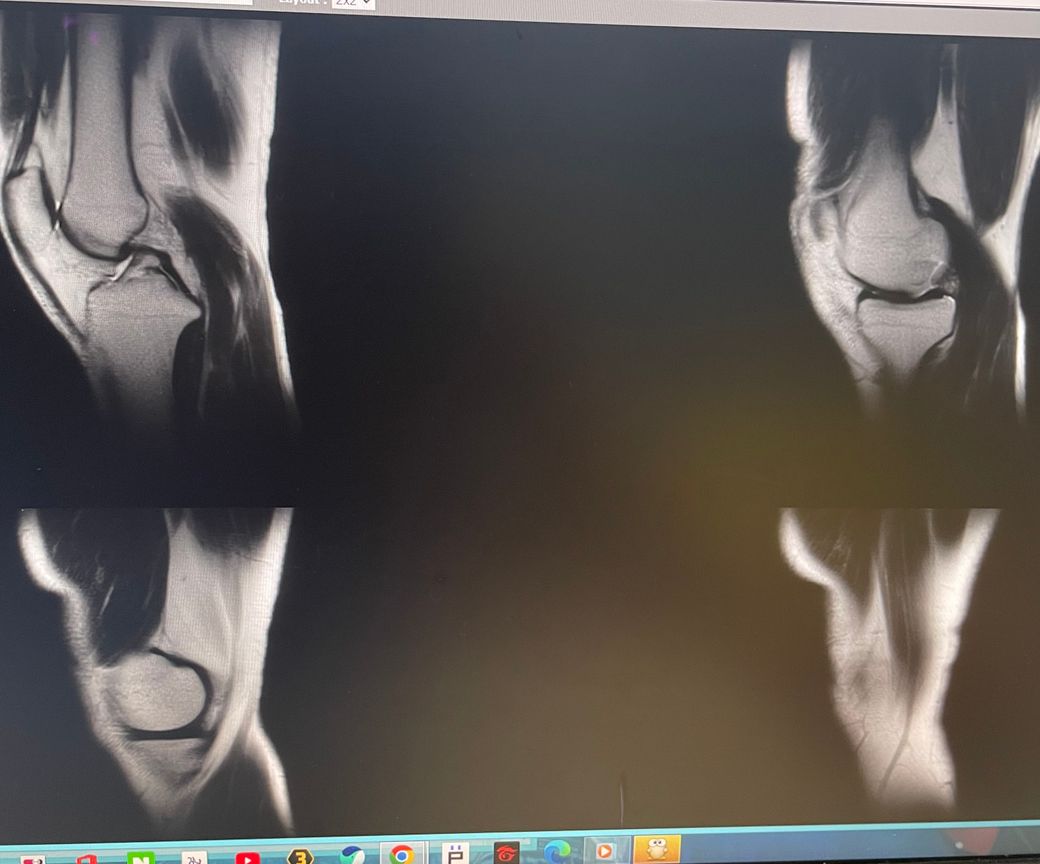

무릎 왼쪽 mri 사진 판독 부탁드리겠습니다.

안녕하세요 3달전쯤에 무릎을 다쳐서 약 한달전에 mri를 찍었습니다.

현재 판독상 인대나 반월연골 손상은 없는 것으로 판독지에 기재되어 있습니다. 임상적인 증상도 중요하니 담당의사와 상의하시고 신검시에 해당과 군의관 판정을 받으시는 것이 좋겠습니다.

십자인대에는 문제가 없지만 반월판의 문제가 있는 것으로 보입니다.

ACL 즉 전방 십자 인대에 불규칙한 소견은 있으나 Tear 즉 십자 인대가 파열되었다는

소견은 관찰되지 않는 상태이며 연골에 퇴행성 변화는 있는 것으로 보이나 이 역시 R/O

으로 확실하지 않음을 의미합니다. 결과적으로 십자 인대의 파열이 명확하지 않는 상태로

군대를 연기할 사유가 될지는 모르며 전방 십자 등 인대 손상의 경우는 명확하게 파열된

소견을 보이지 않는 경우, 군 입대에 문제가 되지는 않을 것으로 생각됩니다.